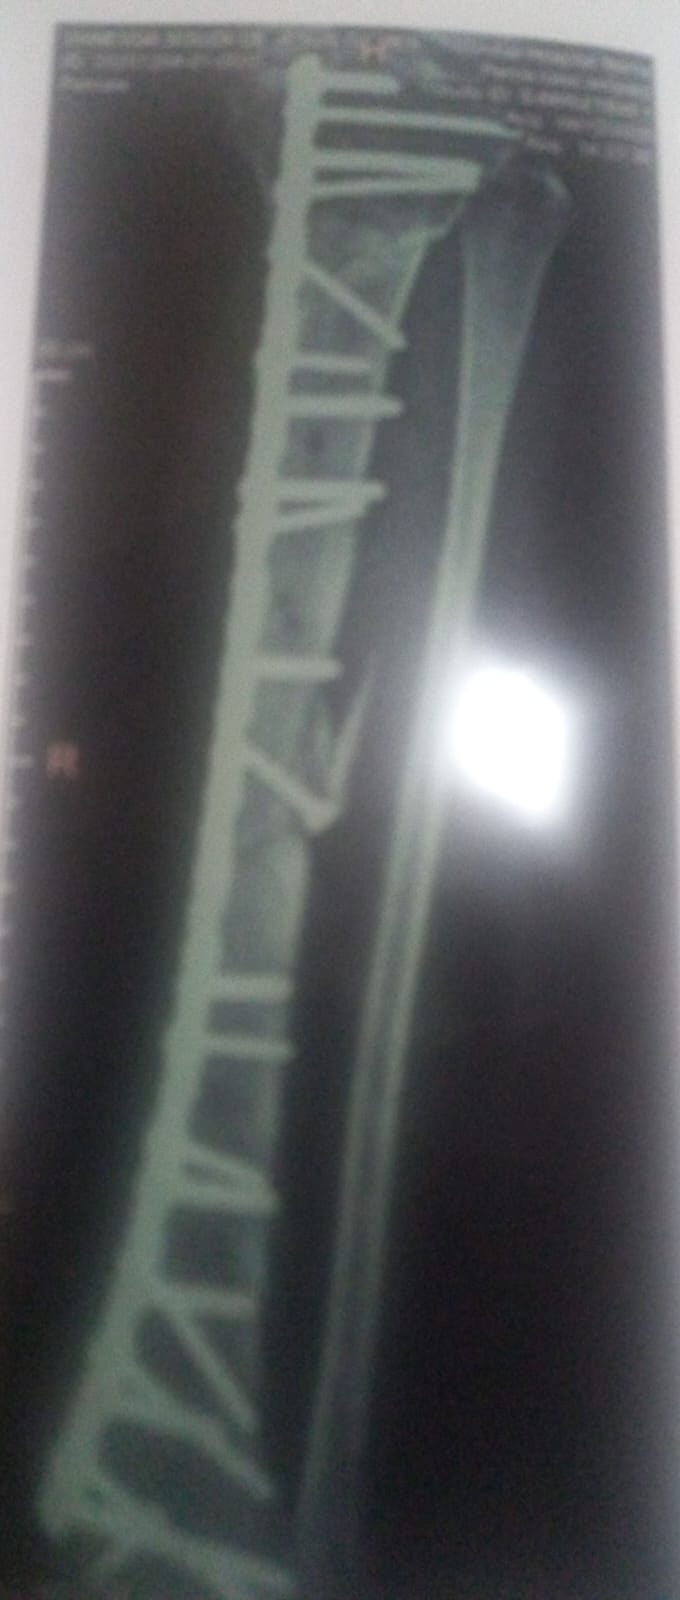

Segundo relatou, sua motocicleta foi atingida por uma caminhonete enquanto ela estava com a filha de seis anos. A criança não sofreu ferimentos, porém Vanessa teve fraturas graves na perna, necessitando da implantação de mais de 20 parafusos e de uma placa que se estende do joelho ao pé.